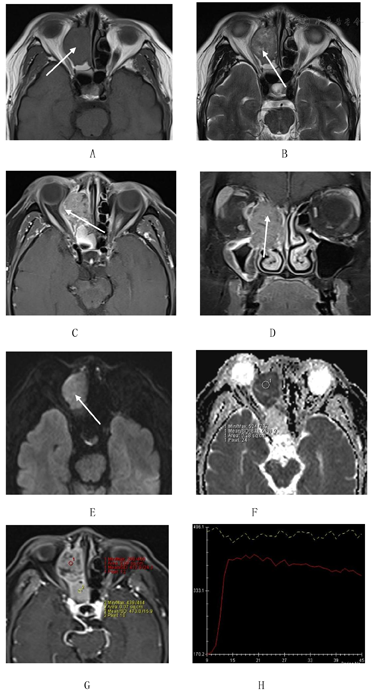

鼻窦CT:右侧筛窦、鼻腔软组织影,累及右侧上颌窦口、额窦及眼眶,右侧眼眶内壁、筛顶、上、中鼻甲及钩突可见骨质破坏。鼻窦MRI:右侧筛窦、鼻腔等T1、等长T2信号影,内部信号不均匀,增强扫描后显示不均匀强化,DWI呈高信号,ADC图呈低信号,ADC值为0.67×10-3mm2/s,动态增强曲线呈"速升流出型",病变累及右侧眼眶、筛顶(图1)。

鼻腔鼻窦NUT癌影像学表现相关文献少见,已发表的文献主要以个案报道或者回顾性分析为主[9]。文献报道[10,11,12]鼻腔鼻窦NUT癌具有恶性肿瘤的特点,CT显示明显骨质破坏,MRI呈混杂信号,增强后不均匀强化,弥散受限。该病例MRI显示病变主体呈等T1等T2信号,明显弥散受限,动态增强曲线呈"速升流出型",以上影像学表现提示小圆细胞恶性肿瘤可能性大。